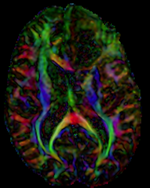

4. set T1 or FLAIR as background and the new DTI_Xf2 volume as foreground

5. Move fade slider to see DTI overlay onto the structural image

DTI aligned with T1Gd DTI aligned with T1Gd

DTI deformation applied (before/after registration DTI deformation applied (before/after registration